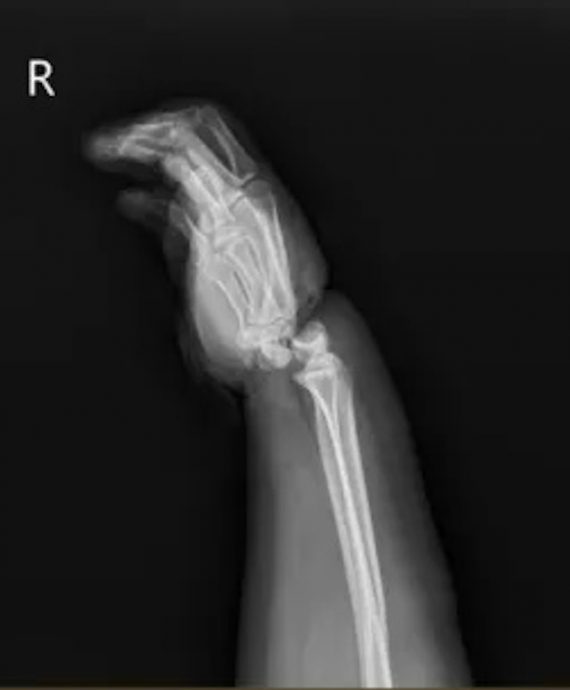

(浙江15日综合电)来自浙江宁波的小美(化名)日前参加亲子拔河比赛时,为更好地发力,便将麻绳绕在右手手腕上,没想到双方发力后,她的手腕被麻绳绞住,被送到宁波市第二医院时,腕关节已完成骨折脱位,被诊断是腕部离断伤。医院马上为她做手术,成功保住右手!

宁波第二医院显微修复外科副主任郭宗慧说,小美入院时右手十分肿胀,手腕严重变形,被绳勒过的皮肤已坏死,手掌因缺血呈现青紫色。经检查发现,小美的腕关节受暴力绞压,两条动脉血管已断,并伴有长段血管损伤,静脉血管出现长段栓塞,手抌关节已完全骨折脱位,有近1公分宽的环形皮肤被挤压坏死。